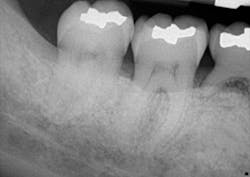

A clinical periodontal and radiographic assessment is completed. Although there is moderate bone loss in all four quadrants, his periodontal status is stable with the exceptions of Nos. 18 and 31 distal (figures 1 and 2). Both areas reveal direct distal probing depths of at least 10 mm and radiographic infrabony distal defects.

Figure 1: No. 18

Figure 2: No. 31

Many periodontists find these defects very predictable to treat with surgery and bone regenerative materials. The high peak of remaining bone provides support, blood supply, and biologic assistance to the grafted area. Conversely, this area tends to be very difficult to treat nonsurgically. Accessing the direct distal of these teeth is extremely challenging, and at depths beyond 5–6 mm, the results of the nonsurgical approach are expected to be poor.